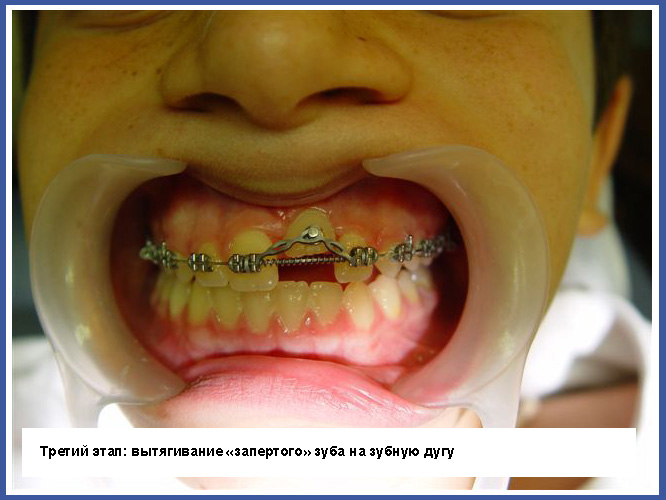

3.Если зуб «заперт» вследствие того, что траектория прорезывания неправильная, нужно обнажить «запертый» зуб хирургическим путем. Иногда простое обнажение зуба может изменить траекторию прорезывания, а иногда во время обнажения нужно приклеивать ортодонтическое приспособление на «запертый зуб» и активно вытягивать его на зубную дугу.